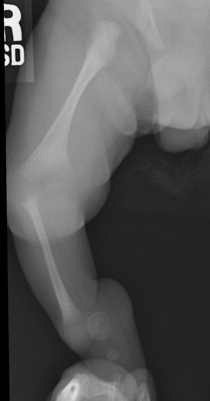

Leg short +++

Tibial Anterolateral Bowing

Foot fixed in severe varus

- can mimic CTEV

- sole facing perineum